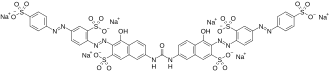

| IUPAC name

Hexasodium (3E)-4-oxo-7-[[(6E)-5-oxo-7-sulfonato-6-[[2-sulfonato-4-[(4-sulfonatophenyl)diazenyl]phenyl]hydrazinylidene]naphthalen-2-yl]carbamoylamino]-3-[[2-sulfonato-4-[(4-sulfonatophenyl)diazenyl]phenyl]hydrazinylidene]naphthalene-2-sulfonate

| C45H26N10Na6O21S6 | |

| Molar mass | 1373.05 g·mol−1 |

Sirius Red F 3B (Direct Red 80) is an azo dye primarily used in staining methods for collagen and amyloid.[1] It has the molecular formula C45H26N10Na6O21S6.